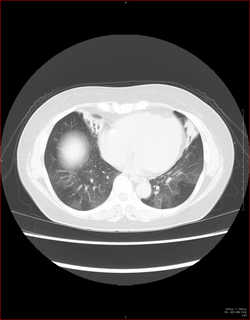

CTで見ると…

3Dだと、こうなります。

気管狭窄ですね。こういう所見もレントゲンで捉えることができるのです。